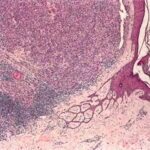

Histopathology of Nodular Melanoma and Common Vertical Growth Phase (Tumorigenic Melanoma) Architectural Features. In a typical tumorigenic melanoma, there is contiguous proliferation of neoplastic melanocytes in the dermis forming a tumor mass that is larger (usually much larger) than the largest nest in the |

Perhaps the best-known single criterion for melanoma is the upward pagetoid extension of tumor cells into the epidermis overlying the melanoma. However, this pagetoid melanocytosis or pagetoid spread is not specific for melanoma (152). Although in nodular melanoma, permeation of the epidermis with tumor cells may be absent or may be limited to that portion overlying the dermal tumor, lateral extension of melanoma cells in the epidermis and papillary dermis beyond the confines of the dermal tumor is seen in the adjacent nontumorigenic compartment of complex primary melanomas [SSM, LMM, acral-Ientiginous melanoma (ALM)]. This phenomenon greatly aids in histologic recognition of these tumors, and, conversely, the recognition of nodular melanomas, which lack this adjacent component, may be difficult. For this reason, nodular melanoma may be difficult or impossible to distinguish from a metastatic melanoma in the skin, and when such a tumor is amelanotic, the distinction from other cutaneous neoplasms may be impossible without immunohistochemistry. |

The amount of inflammatory infiltrate in tumorigenic melanomas varies. As a rule, early invasive malignant and many in situ melanomas show a bandlike inflammatory infiltrate, often intermingled with melanophages, at the base of the tumor. In tumors that extend deep into the dermis, the inflammatory infiltrate is quite variable, but it is often only slight to moderate rather than pronounced. Lymphocytes extending among tumor cells are often associated with morphologic evidence of damage to individual tumor cells (apoptosis). These tumor-infiltrating lymphocytes (TILs) have been shown to have independent favorable prognostic significance . The infiltrate is a predominantly T-cell response . TILs extracted from melanomas (mostly metastatic cases) may be cytotoxic and may be directed against immunogenic melanoma-associated antigens . |

Cytological Features. The tumor cells in the dermis show great variation in size and shape. Nevertheless, two major types of cells can be recognized; an epithelioid and a spindle-shaped cell type. Many tumors show both types of cells, but usually one type predominates. Generally, the lentiginous forms of melanoma (e.g., LMM and ALM) tend to show a predominance of spindle-shaped cells in their invasive dermal components, whereas superficial spreading and nodular melanomas tend to be composed largely of epithelioid cells . The epithelioid type of cell tends to lie in alveolar or nested formations and the spindle-shaped type of cells in irregularly branching formations. The alveolar formations of the epithelioid cells are surrounded by thin fibers of collagen containing a few fibroblasts. Tumors in which spindle cells predominate may resemble sarcomas or other spindle cell tumors but in most cases differ from them by the presence of junctional melanocytic activity. |